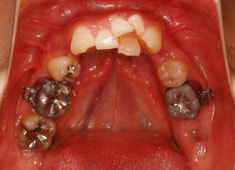

症例紹介

右下7番欠如歯(保存不可能歯につき抜歯)右下8番利用

治療法:フルパッシブブラケット:クリアスナップ

治療開始時